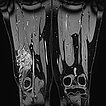

Die koronare, fettunterdrückte T2-Wichtung der Oberschenkel zeigt rechts die intramuskulär gelegene venöse Malformation.